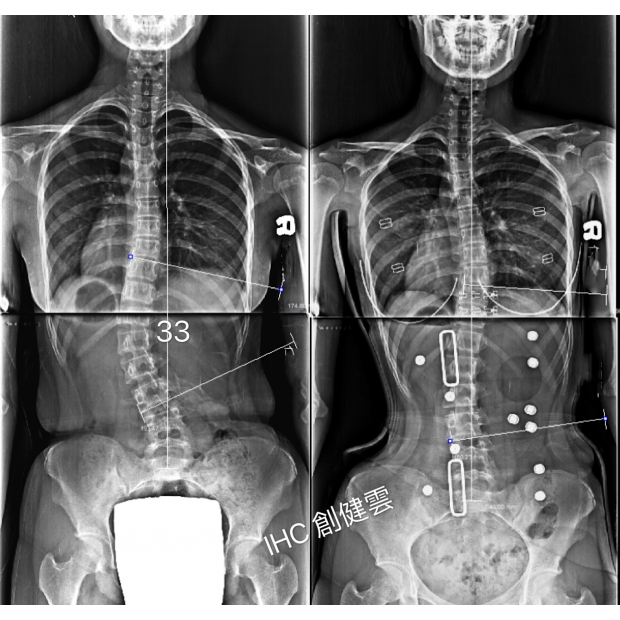

16歲C型脊椎側彎女孩

腰彎33度

20歲脊椎側彎女孩

胸腰彎33度